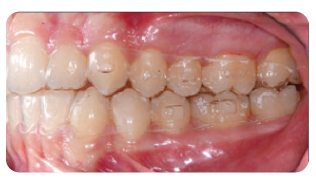

After four months of the Carriere Motion Appliance and full-time intermaxillary elastics, a Class I molar and canine relationship was achieved.